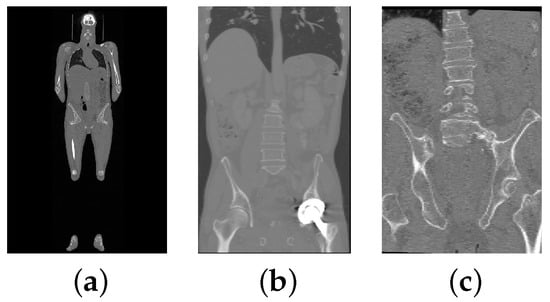

3.1. Image Data

3.1.1. Iowa Data

3.1.2. Verse2020 Data